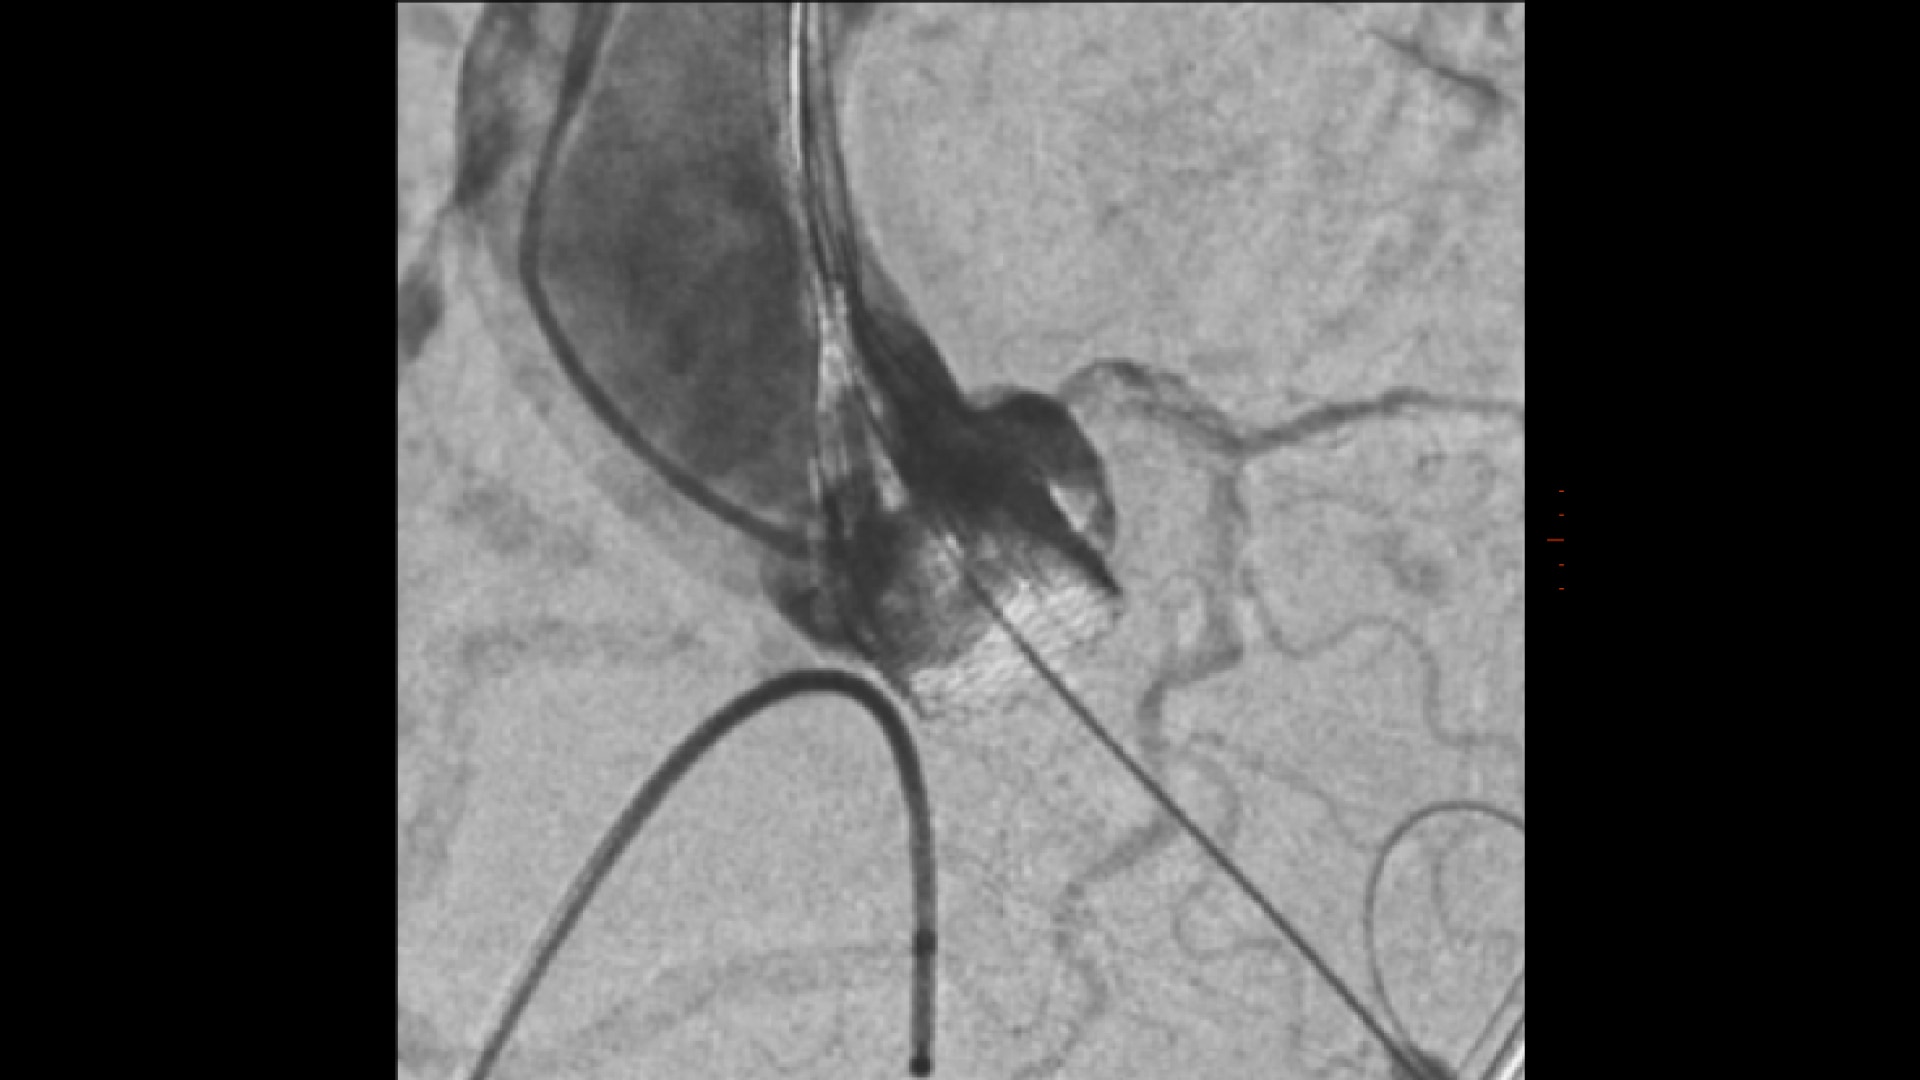

GUIDE

3D fusion guidance enhanced with Calcification Enhancement improves the visualization of moving contrasted structures.

ASSESS

Assess potential regurgitation with exceptional contrast visualization.